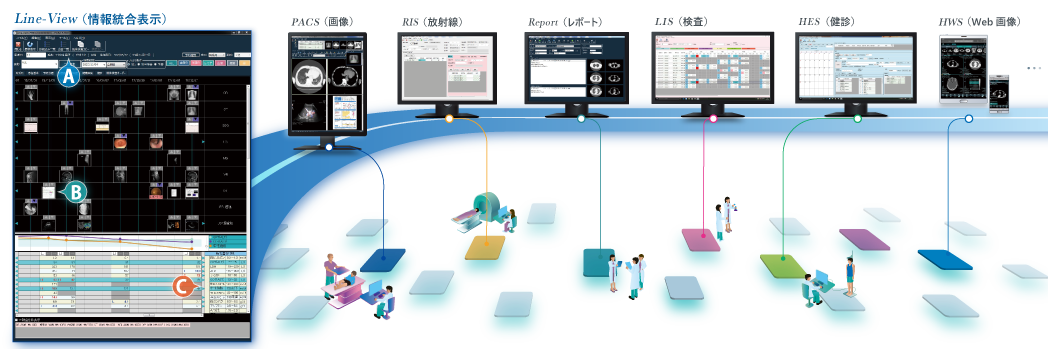

情報統合表示「Line-View」

Line-View情報統合表示:

A:患者ID 単位で時系列結果をサムネイルで表示、全体検査経緯を俯瞰して把握

B:院内モダリティ画像・スキャンデータ・他施設からの紹介メディア取込画像を紐づけて一元管理

C:院内・外の検体検査、健診結果表示、健診受診歴、健診結果報告書も画像ファイリングと同じタイムラインの中で表示

※ 検査システム・健診システム等追加拡張オプションの導入が必要